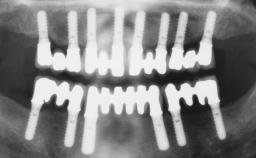

Early Loading of Two Implants in the Mandible and Final Restoration with a Retentive-Anchor-Supported RDP

A 63-year-old male edentulous and maladaptive patient presented with an inability to wear his existing complete maxillary and mandibular dentures. He had been edentulous for 41 years, and there had been three unsuccessful attempts by dentists to provide complete dentures for him. Efforts to wear both complete dentures were always initially encouraging, but over time, he invariably found that he was unable to wear the complete mandibular denture, and this pattern had persisted for 20 years. After seeing local newspaper advertisements, he requested having his complete mandibular denture stabilized with implants.

# of Implants 2

Type of Implants One-Piece

Modality 2 interforaminal implants